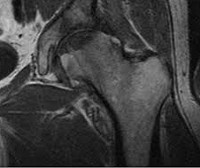

MRI of the hip joint.

МРТ тазобедренного сустава. Современные методы диагностики с использованием электромагнитных волн, для исследования анатомического строения, для оценки состояния структур твердых и мягких тканей суставов бедра и подвздошной кишки. Процедура используется для визуализации ран, опухолей и аномалий развития. МРТ тазобедренного сустава дает информацию о воспалительных, дегенеративных и аутоиммунных процессах с участием мягких тканей, связок и полости сустава. Манипуляция не связана с воздействием радиации, ее можно проводить с контрастом для улучшения визуализации патологических очагов.